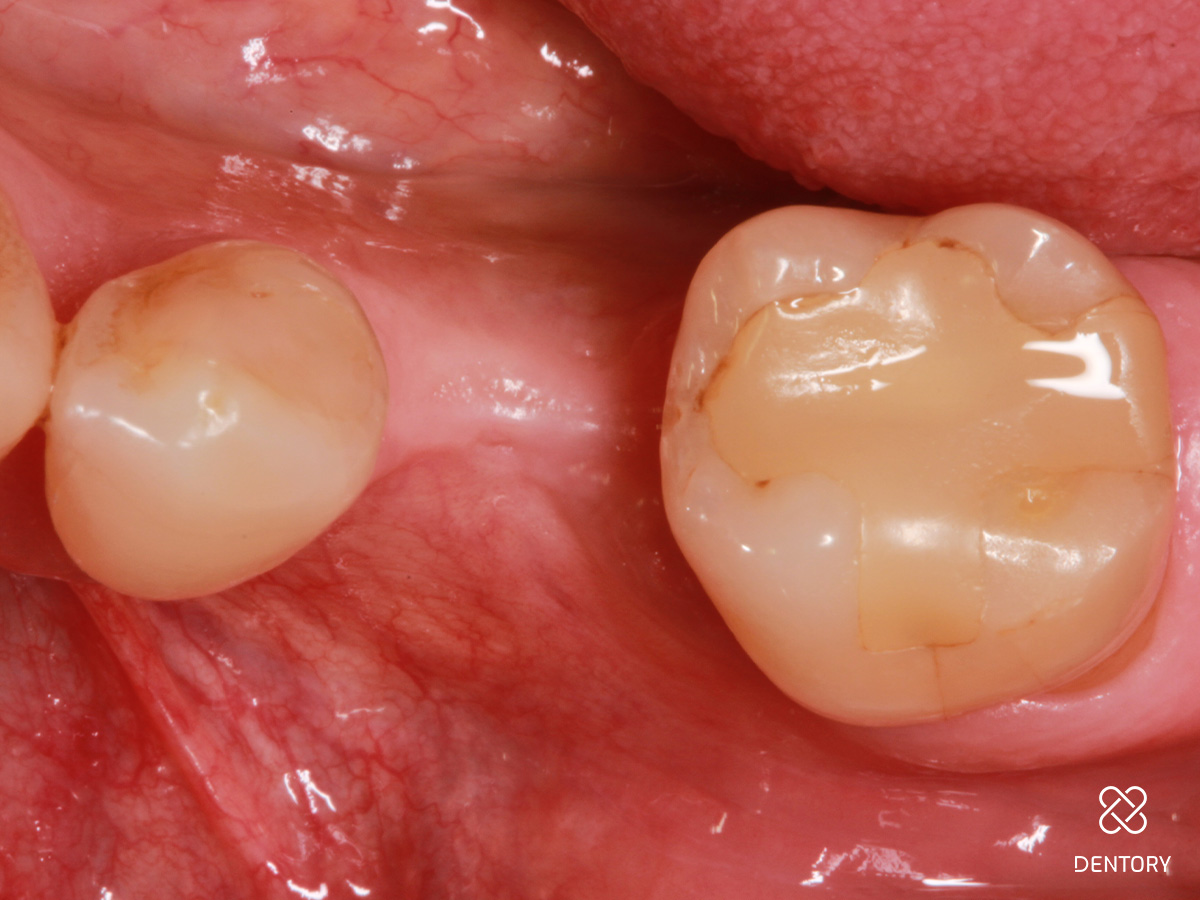

Abbildung 16

Situation vor dem Einsetzen der definitiven Rekonstruktion: Vor dem Einsetzen der definitiven Rekonstruktion zeigen sich gesunde Weichgewebsverhältnisse mit ausreichend befestigter Mukosa für stabile Knochenverhältnisse.